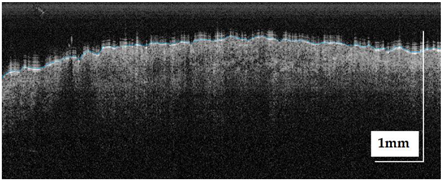

| Superficial spreading melanoma (SSM) Case 1 | Localization: right anterior arm |

![]() | ![]() |